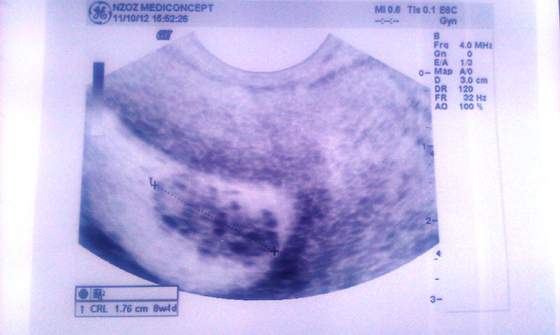

Iownka będzie dobrze. Dbaj o siebie i bądź dobrej myśli.